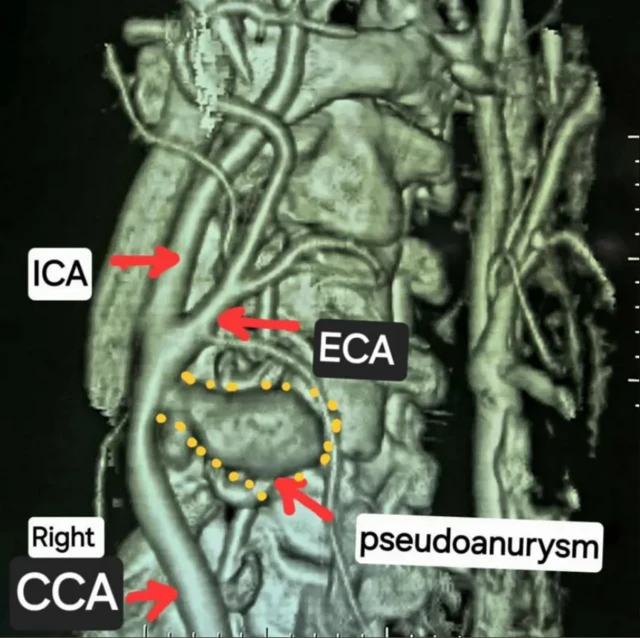

ਤਸਵੀਰ ਸਰੋਤ, Doctor Krishnakant Sahu

ਮੈਡੀਕਲ ਜਾਂਚ ਵਿੱਚ ਸਾਹਮਣੇ ਆਇਆ ਕਿ ਰਾਹੁਲ ਦੀ ਸੱਜੀ ਕੈਰੋਟਿਡ ਆਰਟਰੀ ਫਟ ਚੁੱਕੀ ਸੀ।

ਦਰਅਸਲ ਗਲ਼ੇ ਵਿੱਚ ਮੌਜੂਦ ਸੱਜੀ ਅਤੇ ਖੱਬੀ ਕੈਰੋਟਿਡ ਆਰਟਰੀ ਹੀ ਇਨਸਾਨ ਦੇ ਦਿਲ ਤੋਂ ਦਿਮਾਗ ਤੱਕ ਆਕਸੀਜਨ ਵਾਲਾ ਖੂਨ ਪਹੁੰਚਾਉਂਦੀਆਂ ਹਨ।

ਰਾਹੁਲ ਦੀ ਗਰਦਨ ਵਿੱਚ ਸੱਜੀ ਕੈਰੋਟਿਡ ਆਰਟਰੀ ਦੇ ਫਟਣ ਨਾਲ ਗਰਦਨ ਦੇ ਅੰਦਰ ਤੇਜ਼ੀ ਨਾਲ ਖੂਨ ਭਰ ਗਿਆ ਅਤੇ ਆਰਟਰੀ ਦੇ ਆਲੇ-ਦੁਆਲੇ ਖੂਨ ਭਰਨ ਨਾਲ ਇੱਕ ਗੁਬਾਰੇ ਵਰਗੀ ਬਣਤਰ ਬਣ ਗਈ, ਜਿਸਨੂੰ ਮੈਡੀਕਲ ਭਾਸ਼ਾ ਵਿੱਚ ਸਿਊਡੋਐਨਯੂਰਿਜ਼ਮ ਕਿਹਾ ਜਾਂਦਾ ਹੈ।

ਤਸਵੀਰ ਸਰੋਤ, Doctor Krishnakant Sahu